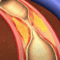

- Τα στεφανιαία αγγεία έχουν μία η περισσότερες σημαντικές στενώσεις που μπορούν να αντιμετωπιστούν με τη διενέργεια αγγειοπλαστικής (συνήθως με τοποθέτηση stent και σπανιότερα μόνο με «μπαλονάκι») και η οποία διενεργείται συνήθως αμέσως μετά την ολοκλήρωση της στεφανιογραφίας.

- Τα στεφανιαία αγγεία έχουν εκτεταμένη νόσο η νόσο σε πολύ κομβικά η τεχνικά δύσκολο να αντιμετωπιστούν σημεία, όπου η επέμβαση αορτο-στεφανιαίας παράκαμψης (by-pass) σε δεύτερο χρόνο, είναι η καταλληλότερη λύση για τον ασθενή.